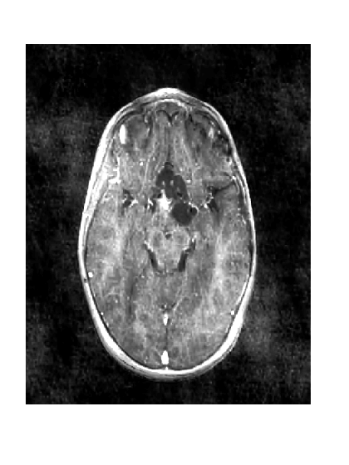

Figure 12: (a) is the ground truth of the follow-up image, (b) is the reference image (with scaling parameter c=2𝑐2c=2), (c) and (d) are reconstructions with η𝜂\eta=0.06 over 3 sampling iterations using LACS-MRI.

Figure 12 shows the effect of a 2-fold scale difference on LACS-MRI image reconstructions. There are extensive streaking artifacts and significant detail is lost compared to the ground truth and the reconstruction using the modified method. Clearly, the Grayscale Compensation for Reference Based MRI Algorithm (GSC) can reduce these artifacts and help improve the visibility of structure.